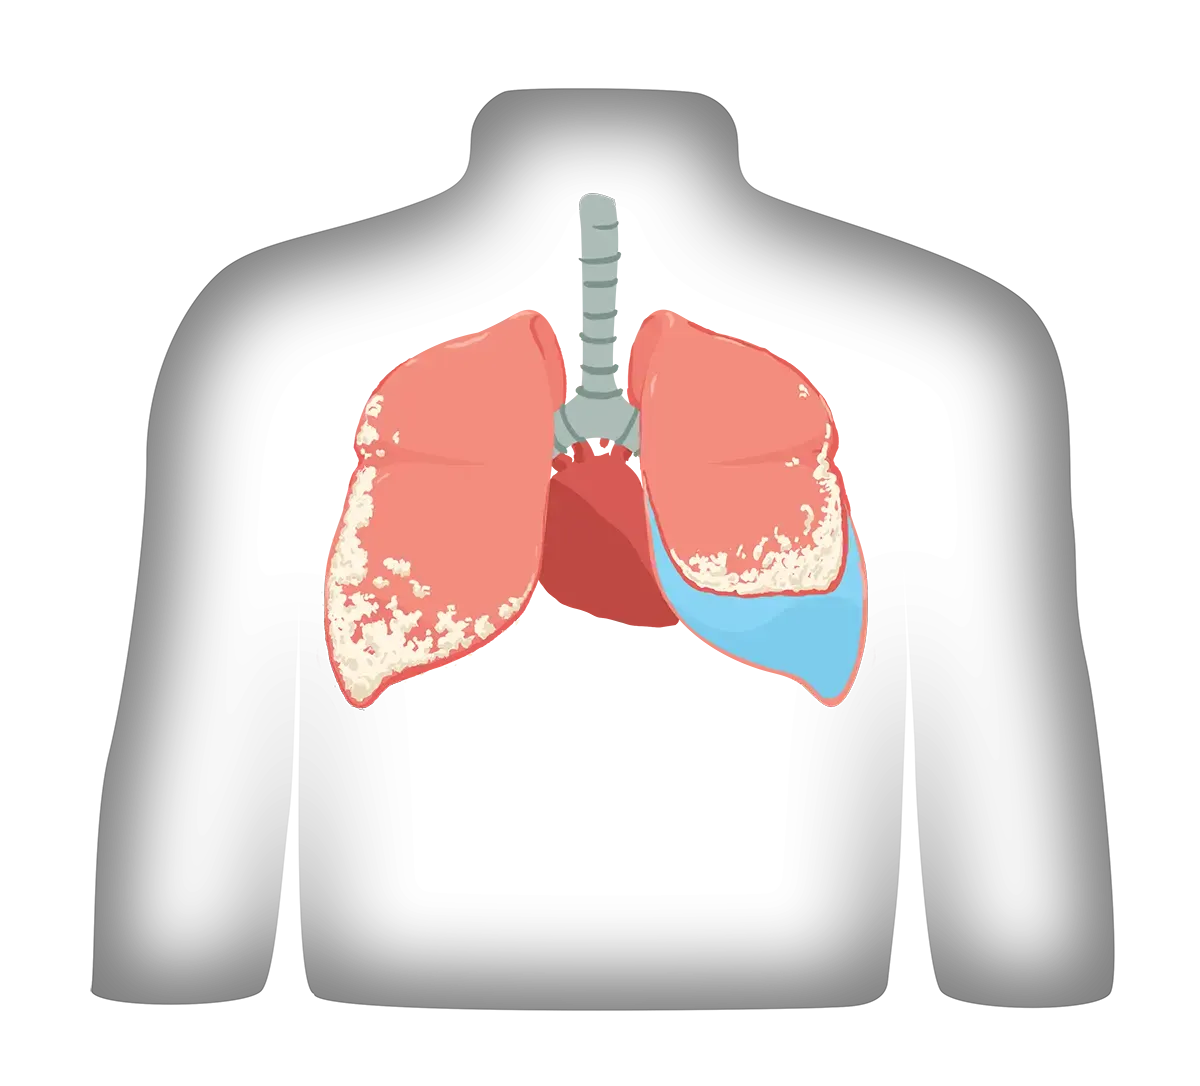

Mesothelioma develops when asbestos fibers lodge in the mesothelium, causing it to form a thickening or mass. This triggers an inflammatory process causing fluid to build up.

If this occurs in the pleura (pleural mesothelioma), fluid builds up in the lungs causing pleural effusion, and the lungs no longer function normally. Fluid will need to be drained periodically. Similarly, fluid can build up in the sac that surrounds the heart, causing pericardial effusion.